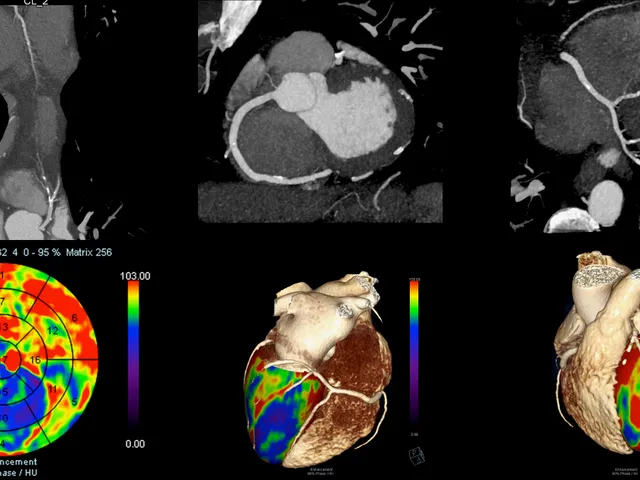

This level 3 Cardiac CT Imaging course is an immersive online programme designed for cardiologists, radiologists, and healthcare professionals aiming to deepen their expertise in cardiac CT imaging. Participants will master advanced techniques, including coronary CT angiography (CCTA), plaque characterization, myocardial perfusion imaging, and the evaluation of structural heart diseases.

The curriculum combines didactic lectures, hands-on training, and case-based learning, with exposure to material from state-of-the-art imaging technologies. Sessions will focus on CT technique, scan acquisition, post-processing, and interpretation under the guidance of expert faculty. Structured reporting and comprehensive case reviews will reinforce diagnostic proficiency and integration with clinical data.

• Master Advanced Cardiac CT Techniques: Gain proficiency in acquiring and interpreting cardiac CT images, including coronary CT angiography (CCTA) and myocardial perfusion imaging.

• Develop Post-Processing Skills: Acquire expertise in post-processing techniques, including 3D reconstruction, stent evaluation, and plaque analysis, using advanced imaging software.

• Didactic Sessions: Introduction to cardiac CT: Basic principles, radiation safety, and image acquisition; advanced coronary anatomy and interpretation of coronary artery disease; role of cardiac CT in pre- and post-procedural evaluation of coronary interventions; evaluation of non-coronary cardiac structures: valvular disease, myocardial disorders, congenital heart disease, and pericardial pathology; emerging technologies: dual-energy CT, fractional flow reserve (FFR) CT, and perfusion imaging.

• Hands-on Training: Practical experience in cardiac CT interpretation; supervised sessions reviewing real-world clinical cases; post-processing techniques: plaque analysis, stent evaluation, and advanced 3D imaging.